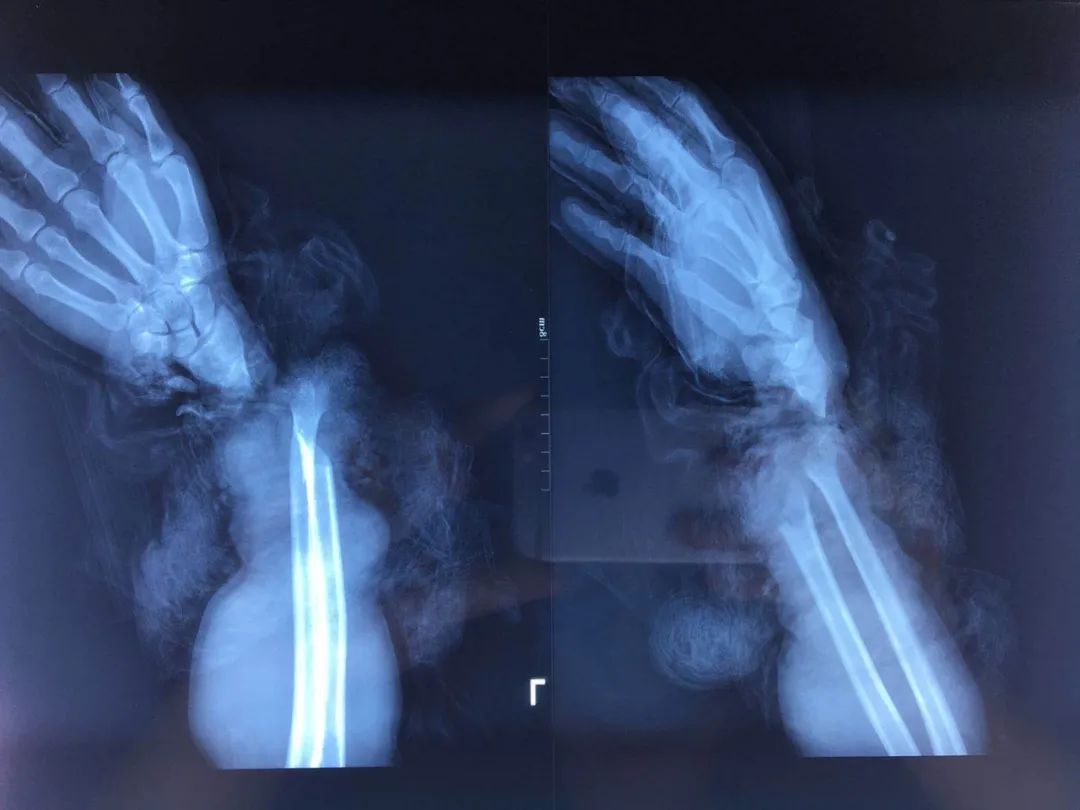

2019年腊月二十一,临近年底,汪先生在工作中突发意外,因机械伤左手手腕完全离断,紧急拨打120后,送往济宁市第一人民医院就诊。当时是中午12点多,到达医院半个小时就完善了相关检查,被紧急推往手术室。

情况危急,如果第一时间不能将血管、神经、肌腱接上,整个手就没法保住,血管神经薄如蝉翼,各种肌腱交纵错杂,伤口污染严重,手术难度可想而知。曾文超团队认真分析伤情、确定手术方案,无影灯下,断腕再植术立即启动,9个小时的奋战中,曾文超及其团队医生一点点地寻找、桥接、缝合,直到所有断裂破损的血管全部吻合恢复通血。凌晨12点多,断腕再植手术完成,末梢指腹充盈良好,血供良好。手术中吻合动静脉6根及数条毛细血管、神经3根、修复屈伸肌腱20多根,有效挽救了患肢功能。